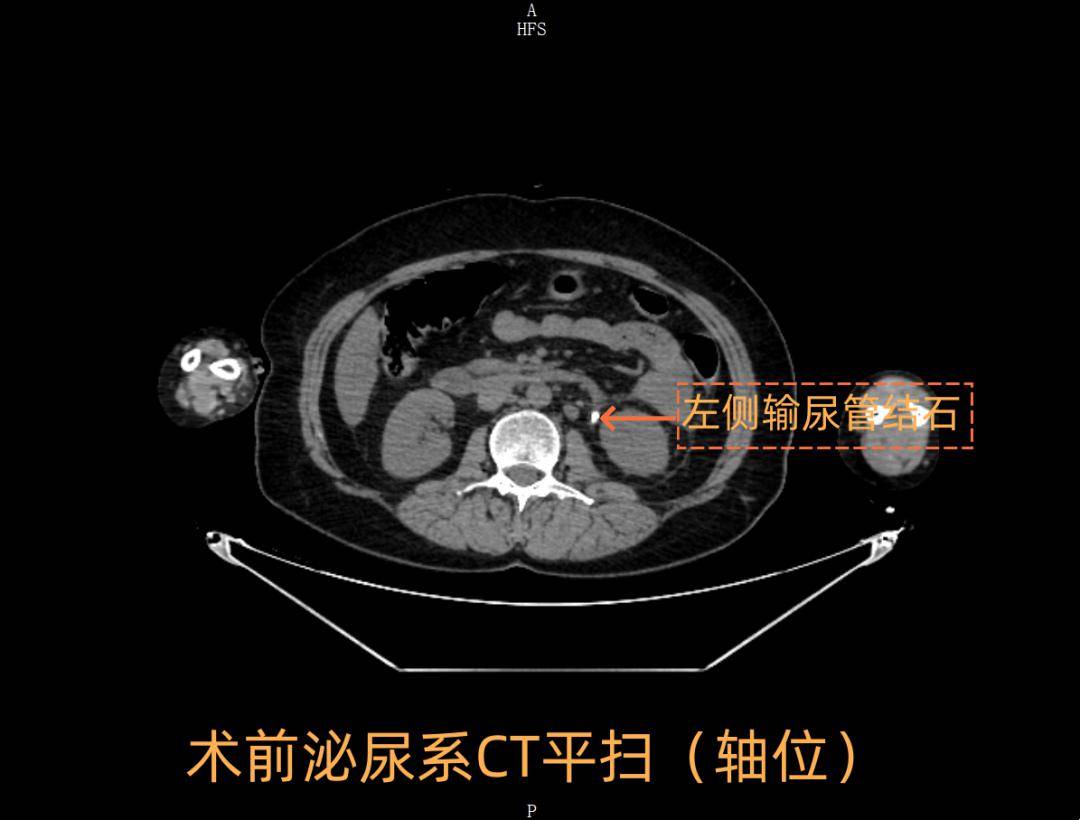

中西医协同攻克重症91 | 与"死神"赛跑!